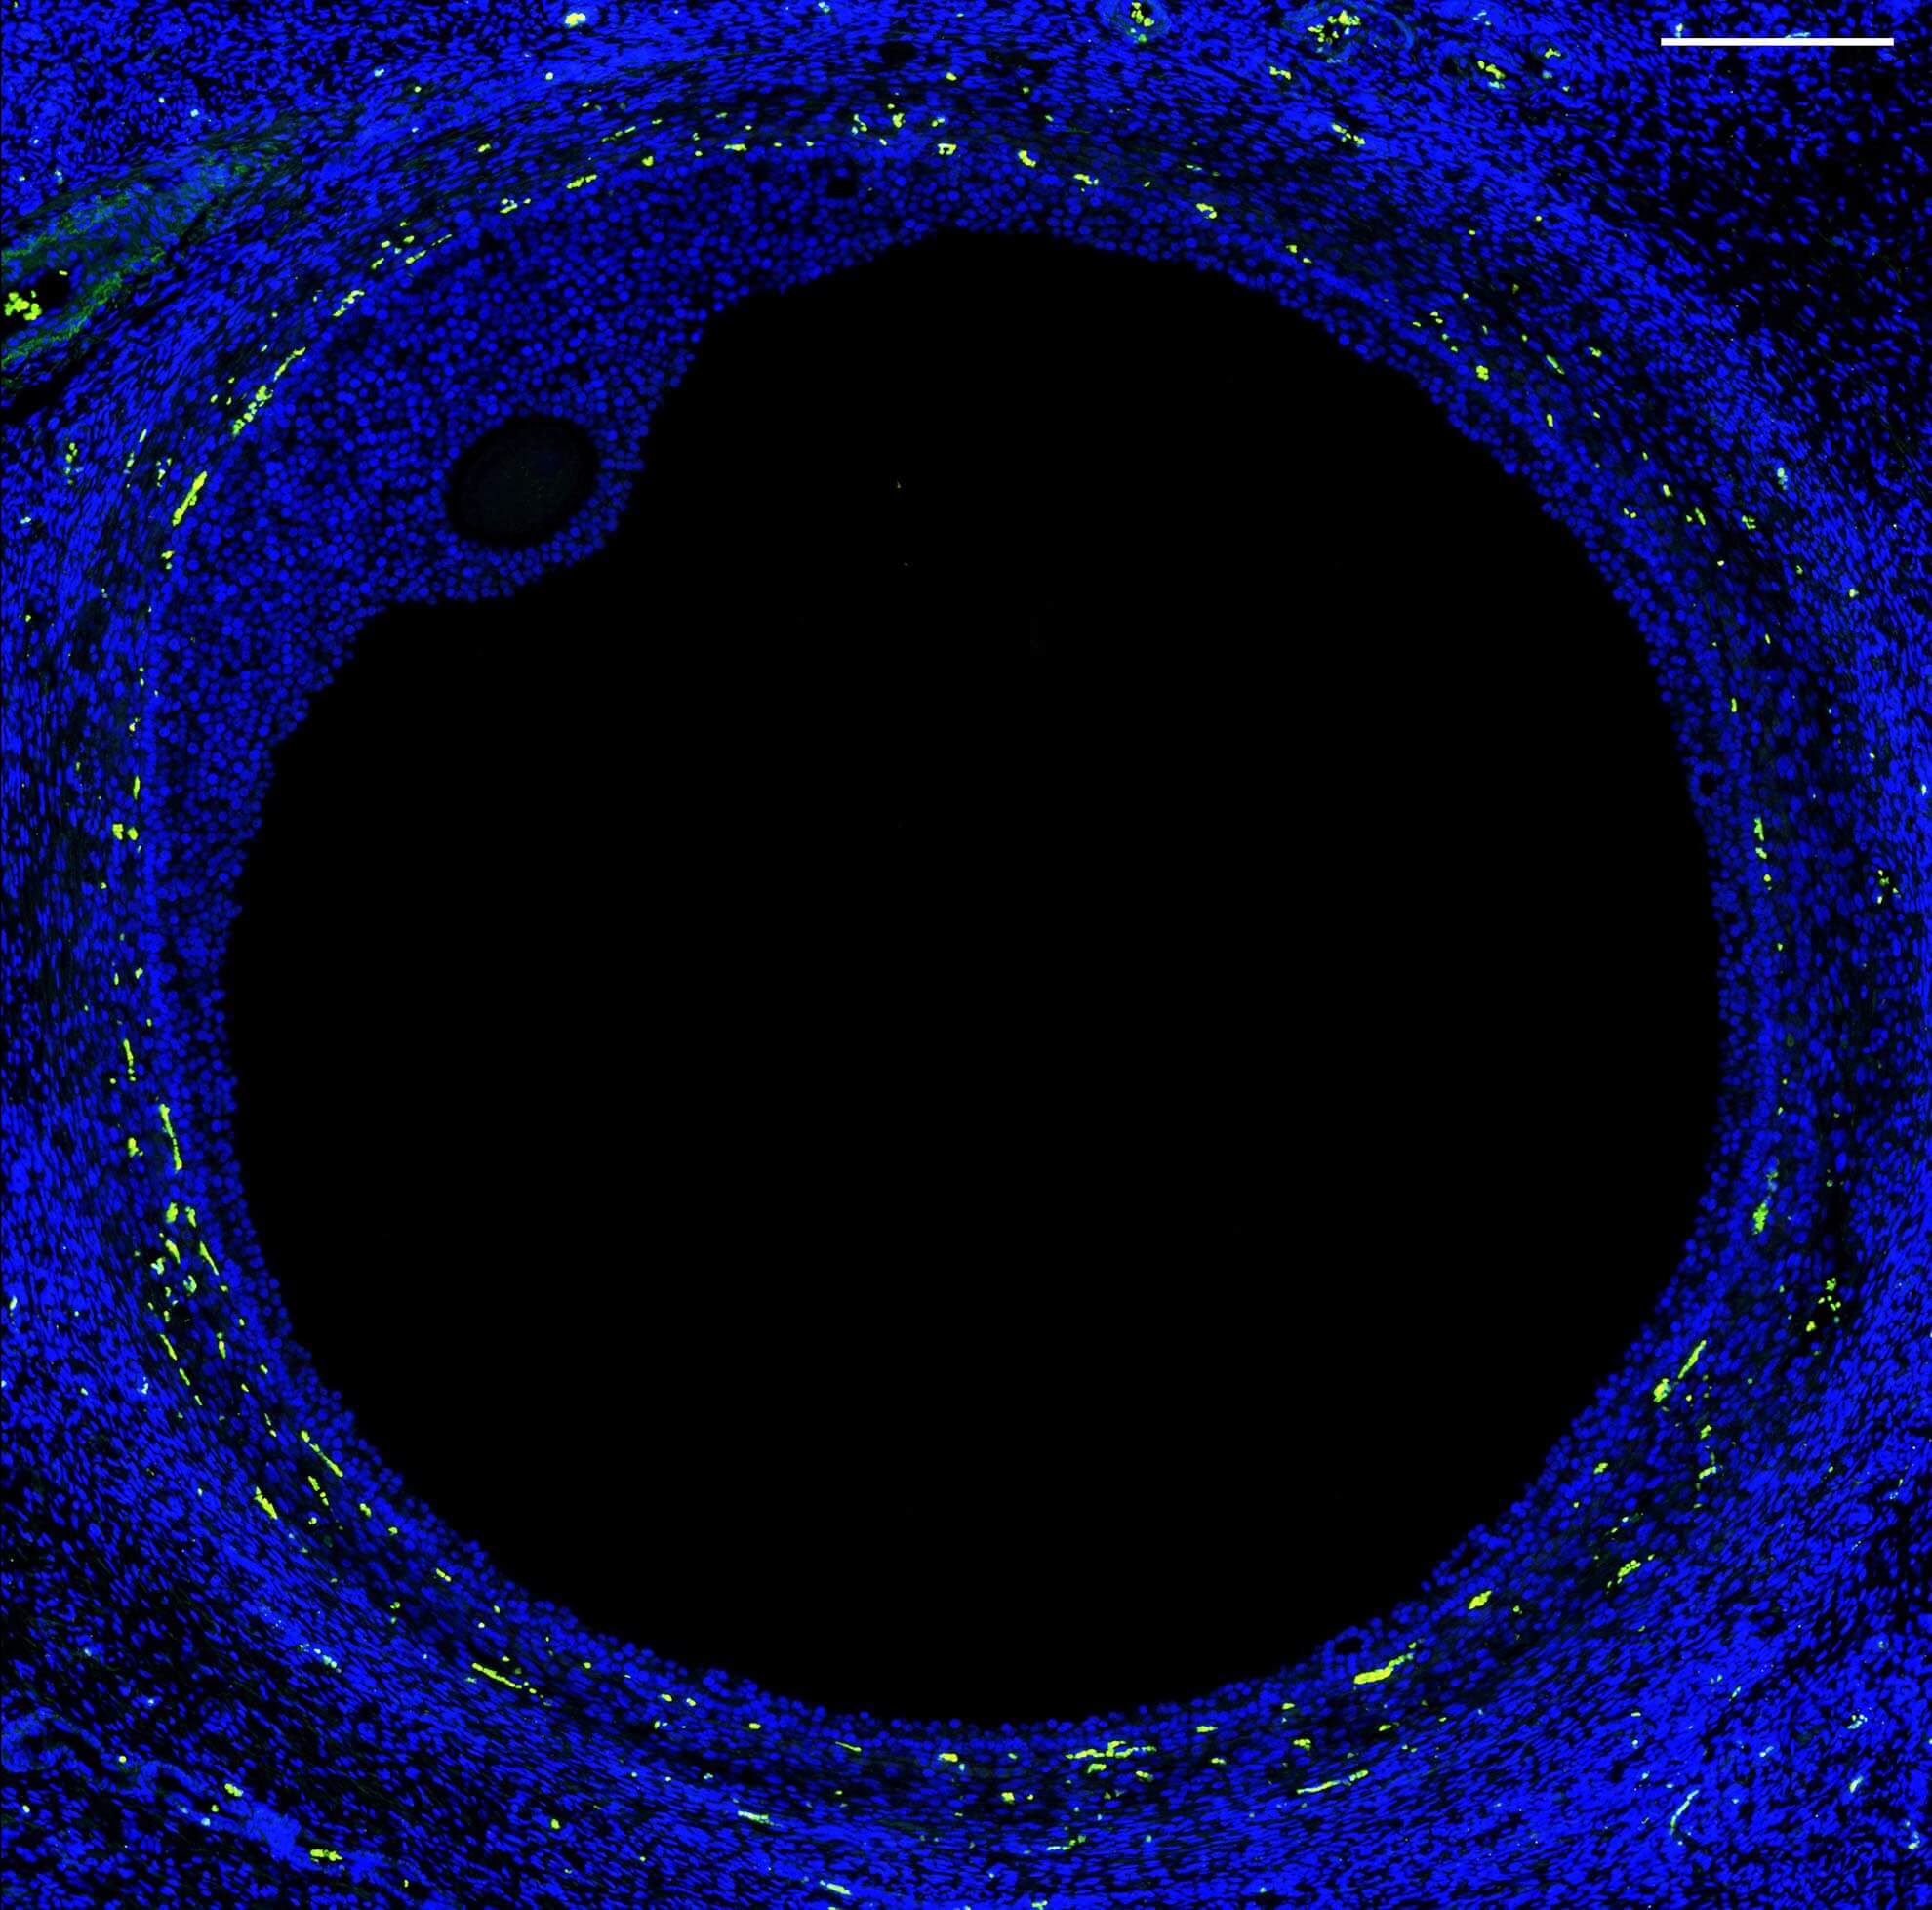

A new effort to characterize the fallopian tube is expanding our knowledge of reproductive health and our ability to treat infertility and reproductive diseases. The project is a collaboration between University of Michigan geneticists Sue Hammoud and Jun Li, clinician Erica Marsh and biomedical engineer Ariella Shikanov. They are working toward a human cell atlas of the female reproductive system.

The team used single-cell RNA sequencing to characterize the diversity of cell types in the fallopian tube — the site of fertilization. They identified 12 major cell types in healthy fallopian tissue, including several new types of epithelial cells with finger-like projections that help egg cells travel from the ovary to the uterus. They also found two types of progenitor cells, which can replenish or repair tissue.

“This really is a basecamp to launch future studies,” Jun says.

Future research could focus on understudied conditions such as infertility, endometriosis and ovarian cancer. In fact, initial findings from the fallopian cell atlas suggest the cellular roots of ovarian cancer may be in the fallopian tube. The researchers identified transition cells that could become cancerous under the right conditions.